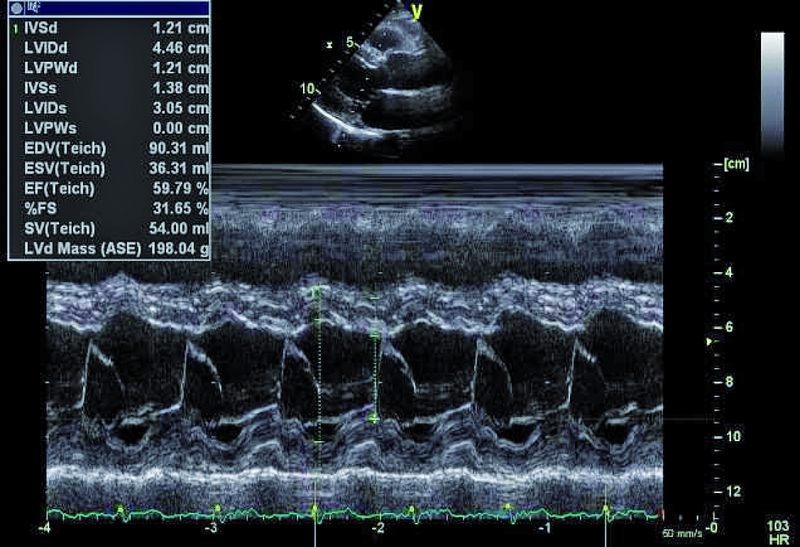

Podstawowym celem terapii jest opanowanie procesu zapalnego. Zazwyczaj kilkutygodniowe (4-6 tygodni) podawanie antybiotyku pozwala osiągnąć taki cel. Należy jednak spytać o wskazania do leczenia operacyjnego. Niezwykle ważna w ocenie jest wielkość wegetacji. Zgodnie ze standardami wskazaniem do operacji jest wegetacja większa niż 15 mm lub wegetacja >10 mm, która stanowiła źródło zatorowości. Żadne z dwóch kryteriów nie było u chorej spełnione. Nie było także epizodu duszności, obrzęku płuc ani innych objawów niewydolności serca. Niedomykalność mitralną oceniono na umiarkowaną. Charakterystyczne dla niej były dwa strumienie fali zwrotnej – jeden centralny wynikający z perforacji płatka tylnego oraz drugi równoległy do płaszczyzny pierścienia zastawki, wynikający z wypadania płatka (ryc. 5). Jama lewej komory była niepowiększona, a kurczliwość mięśnia prawidłowa (ryc. 6). Zdecydowano o postępowaniu zachowawczym z kilkutygodniową skojarzoną antybiotykoterapią. W toku obserwacji zaplanowano kolejne badanie przezprzełykowe z oceną ewentualnej zmiany wielkości wegetacji.